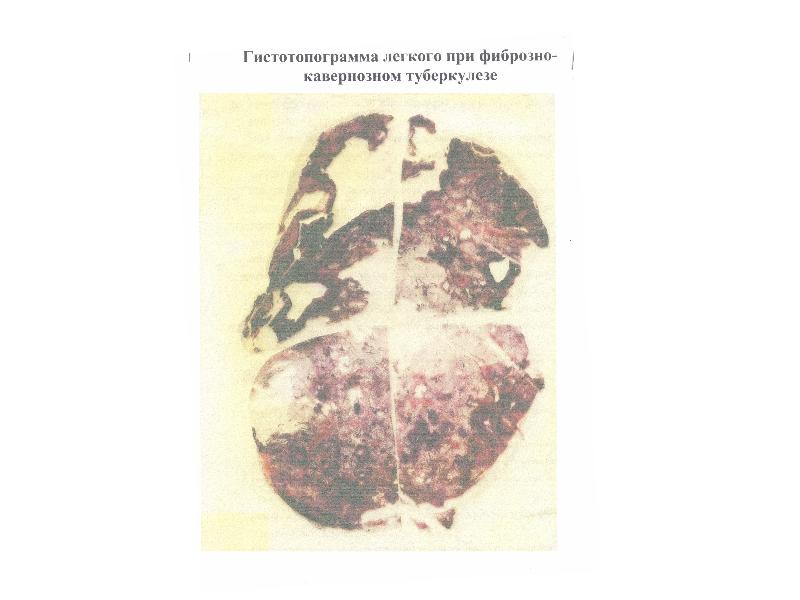

Понимание кавернозного туберкулеза почки

Раздел: Мудрость в деталях